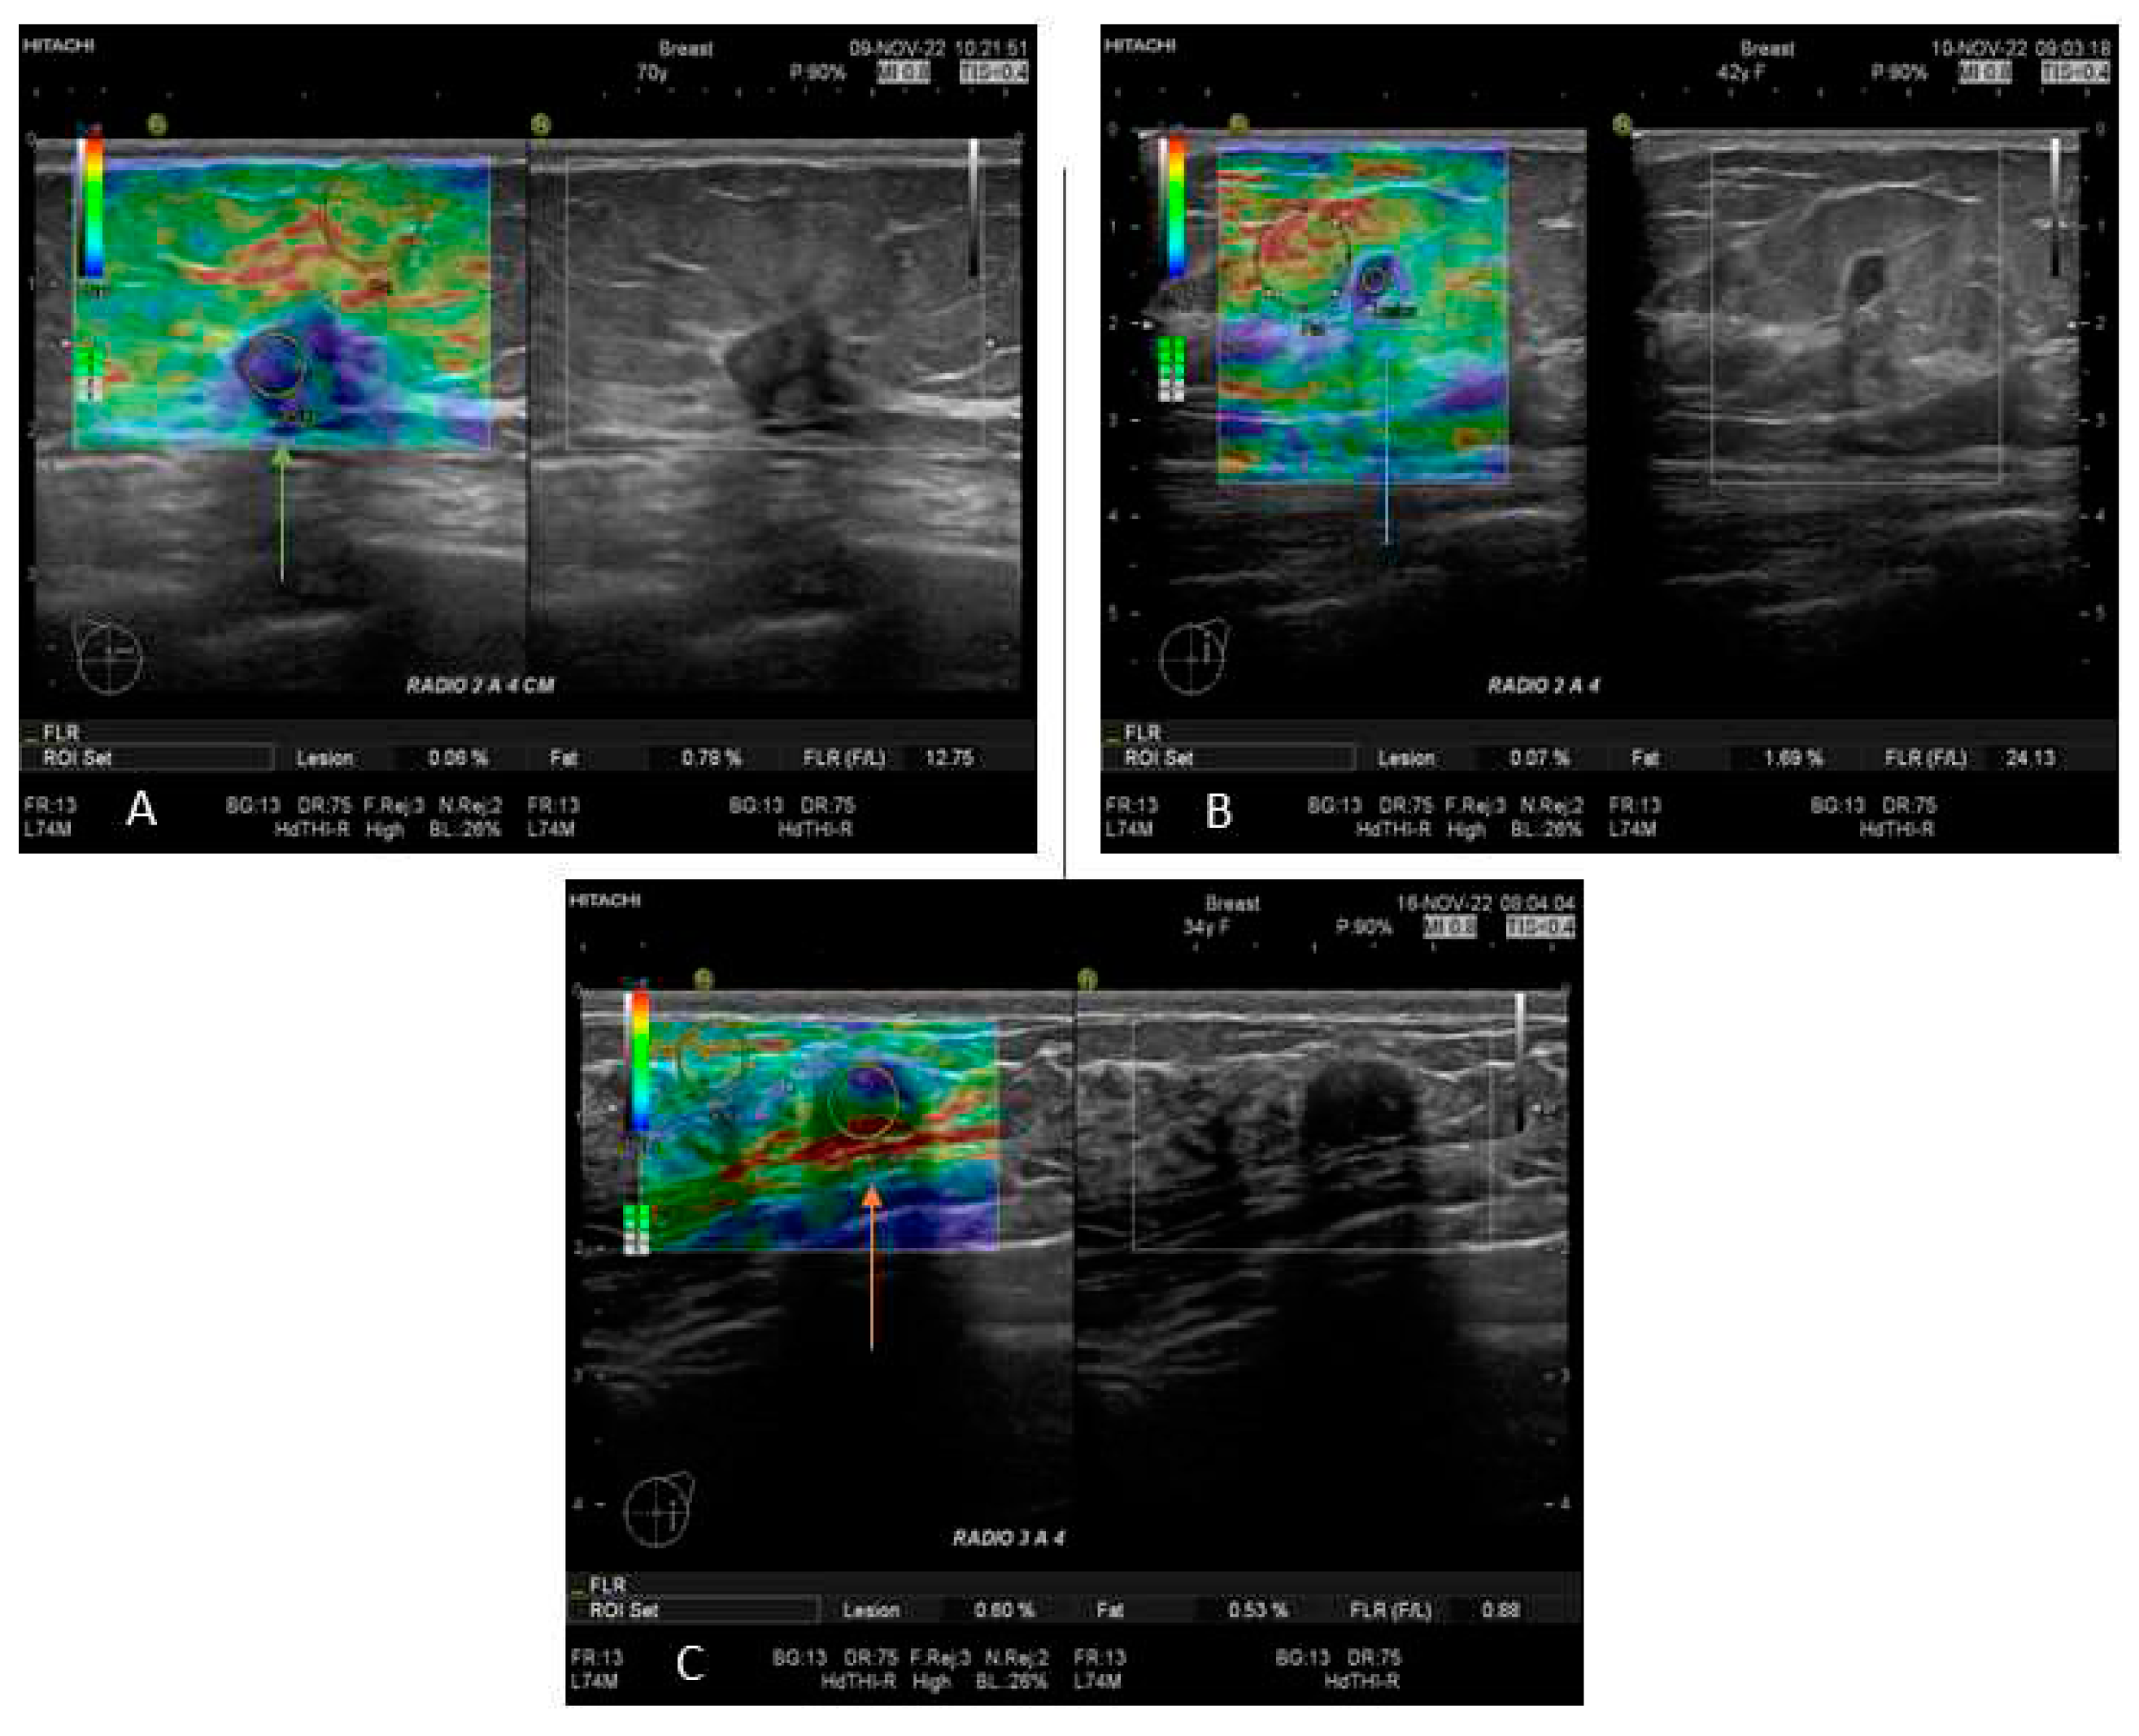

Figure 1. Images of B mode US and SE, corresponding to A) TN tumor in a female of 70 years old (green arrow) with F/L index 12.75; B) Luminal A tumor in a female of 42 years old (blue arrow) and C) Negative biopsy in a female of 34 years old (orange arrow).

In this study, all patients with any mass or suspicion of them were exposed to US exploration and SE; those studies were performed by 3 radiologists with more than 15 years of experience in breast imaging. All measurements and images were acquired with a Hitachi Avius (Hitachi Medical, Tokyo, Japan) equipped with a multifrequency linear transducer from 7 to 12 MHz, with color Doppler and elastography by placing the transducer on longitudinal scans. We use semi-quantitative elastography in all patients, measuring three times with slight compression according to the World Federation for Ultrasound in Medicine & Biology (WFUMB) Guidelines, obtaining a final average (Figure 1) [16]. All lesions were classified by the 5th edition of Breast Imaging Reporting and Data System (BI-RADS), where category 2 is benign, category 3 is probably benign, category 4 is suspicion of malignancy and is segmented in 4A (low suspicious for malignancy), 4B (moderate suspicious for malignancy), and class 4C high suspicious for malignancy (in all of them, biopsy is required), and category 5 is highly suspicious for malignancy (biopsy mandatory)[17]